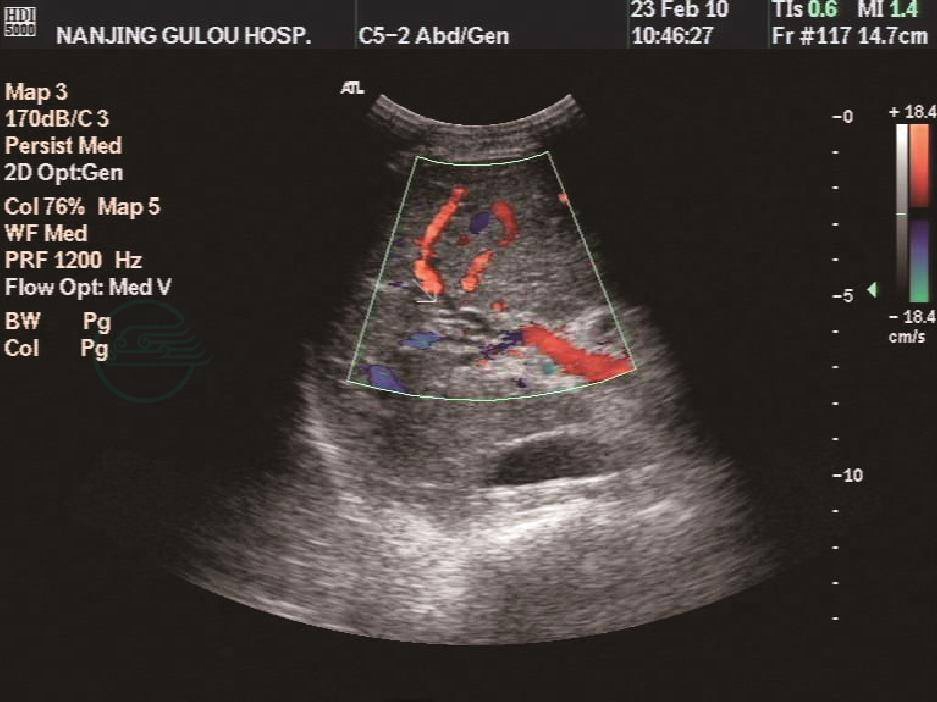

血管超声:门静脉直径0.91cm,主干及左右支的近段内透声好,管壁增厚,CDFI示为肝性单向血流,多普勒频谱示血流速度33.2~21.5cm/s。门静脉左右支的远段及小分支正常结构消失,呈扭曲的条索样结构(图1,图2),诊断门静脉发育异常。CDFI:静脉频谱,血流流速减慢。下腔静脉彩色血流多普勒检查:未见异常。

图1 腹部超声显示CDFI为肝性单向血流

图2 门静脉右支的远段及小分支正常结构消失,呈扭曲的条索样结构